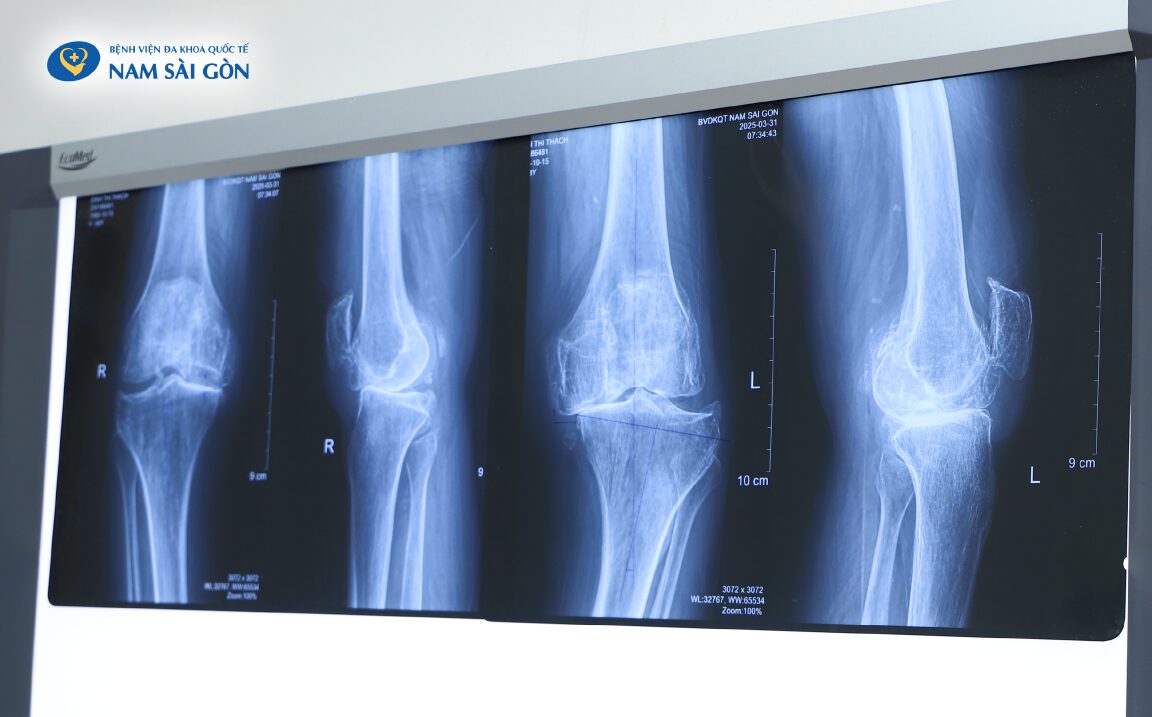

Hình ảnh phim chụp X-quang của người bệnh trước khi được phẫu thuật

Không muốn trở thành gánh nặng cho con cháu, bà T. quyết định tìm đến Bệnh viện Đa khoa Quốc tế Nam Sài Gòn. Tại đây, BS.CKII Võ Văn Mẫn – Trưởng khoa Chấn thương chỉnh hình, đã trực tiếp thăm khám và xác định tình trạng thoái hóa khớp gối độ 4 hai bên – mức độ nặng nhất, kèm theo hội chứng Cushing, loãng xương, đái tháo đường và tăng huyết áp do lạm dụng corticoid.